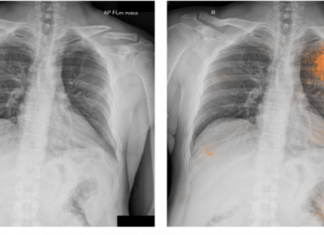

醫療 AI 獨角獸 HeartFlow 的心臟血流分析軟體獲 FDA 批准

冠心病經常漏診與誤診,之所以讓醫生難以診斷,是因為目前的檢測手段仍採用侵入性和高成本的血管造影。